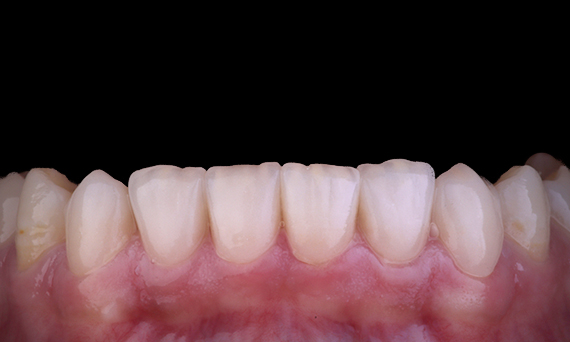

È abbastanza comune osservare crepe e fratture associate ai restauri in amalgama, in particolare quando aumentano di dimensioni in quanto sono restauri “non coperti dallo strato adesivo”. Molti di questi denti sono strutturalmente compromessi e un approccio adesivo e biomimetico è il metodo ideale per ripristinare questi denti. Nell’ambito di un piano di trattamento più completo, si prevedeva che questo quadrante avesse due onlay indiretti in ceramica. Il primo e il secondo molare sono stati ripristinati in una singola visita utilizzando CEREC Tessera, un disilicato di litio avanzato.

Dott. Yo-Han Choi, Sidney, Australia